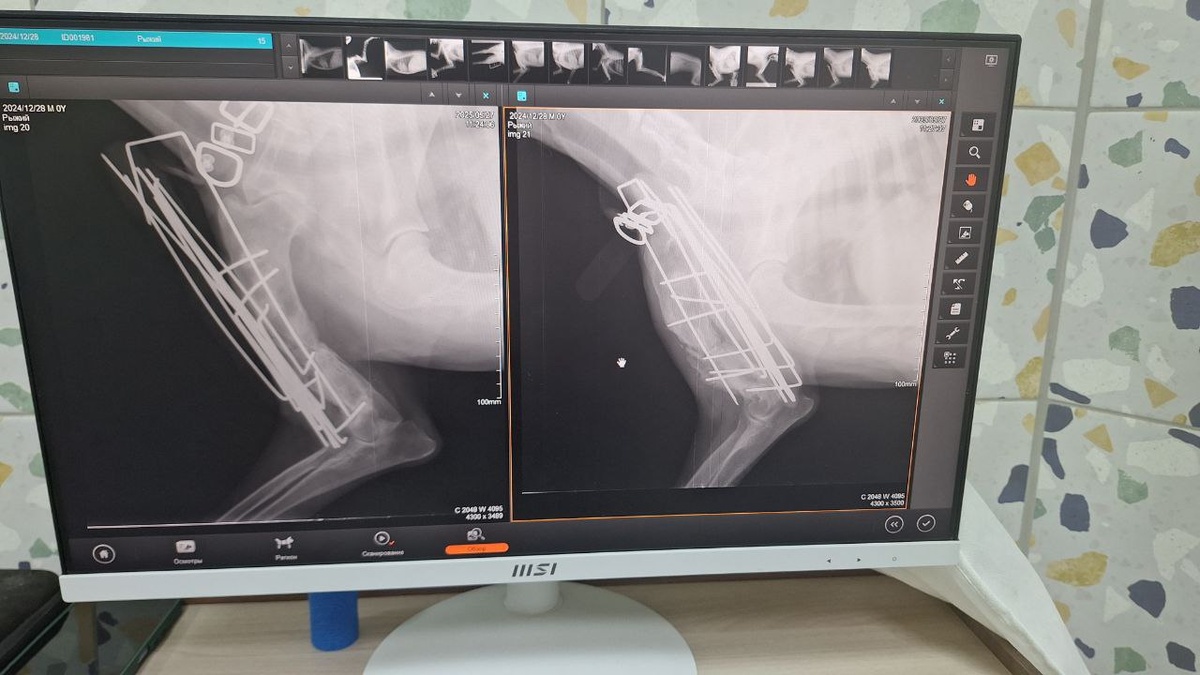

Сегодня мы с Лео посетили клинику ВВЦ. Сделали рентген в двух проекциях, и, как вы можете видеть, кость ещё не полностью срослась. Поэтому аппарат пока снимать рано. Мы записались на приём через месяц.

Чтобы ускорить процесс восстановления, врач посоветовал помогать Лео опираться на лапку — показал, как это делать. Также необходимо приобрести кальциевую добавку.